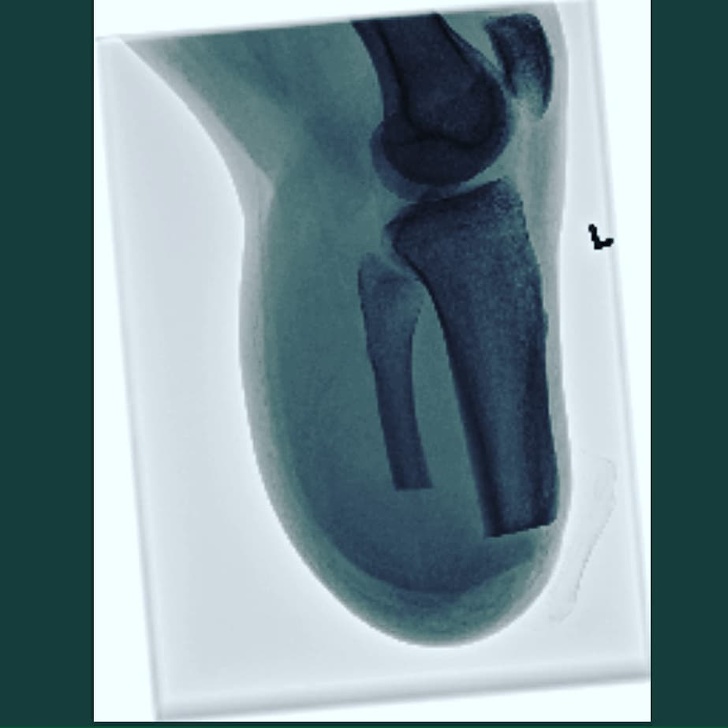

Отримав рентгенівські знімки своєї ампутованої ноги